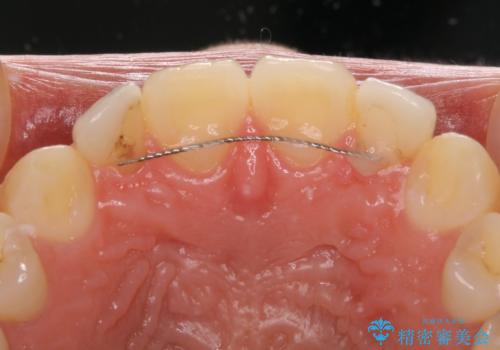

着色の原因として、湿気の多い環境で接着操作を行うと、境目に細かいギャップができてしまうことが考えられます。

接着の際にはラバーダムを使用して、乾燥した環境を整えて処置を行いました。